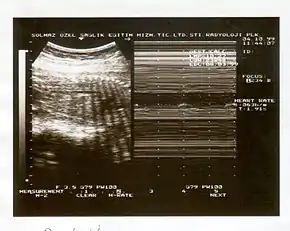

A biophysical profile (BPP) is a prenatal ultrasound evaluation of fetal well-being involving a scoring system,[1] with the score being termed Manning's score.[2] It is often done when a non-stress test (NST) is non reactive, or for other obstetrical indications.

The BPP has five components: four ultrasound (US) assessments and an NST. The NST evaluates fetal heart rate and response to fetal movement. The five discrete biophysical variables are:

1. Fetal heart rate